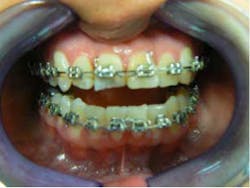

She came to me for an orthodontic consultation. She was 24 years old and hoping to marry her then-boyfriend at some point, but she didn't like her smile; she felt it was unattractive. So we gathered her orthodontic records and pointed out to her that it appeared she had either a supernumerary tooth or over-retained primary tooth between her upper centrals. Along with this, she also had some minor crowding on her lower teeth. She had a Class I molar relationship that I hoped to maintain.

Month 0-3 I like to start all my orthodontic cases off with a light round nickel titanium wire such as an 014N or 012N. While in this wire, I used some elastomeric chain to help align and rotate the teeth.Month 4-10 I continued to level the teeth and begin to reposition brackets on a 18X25 heat-activated NiTi wire based on a panoramic X-ray that I like to take to help me with root positioning.Month 11-16 Progress to a stainless steel 19x25 wire for more tooth torque and better bracket engagement.Month 16-18 Finishing on a 018SS. I don’t have much wire-bending skills, so I mostly move brackets and am capable of only some simple step bends.